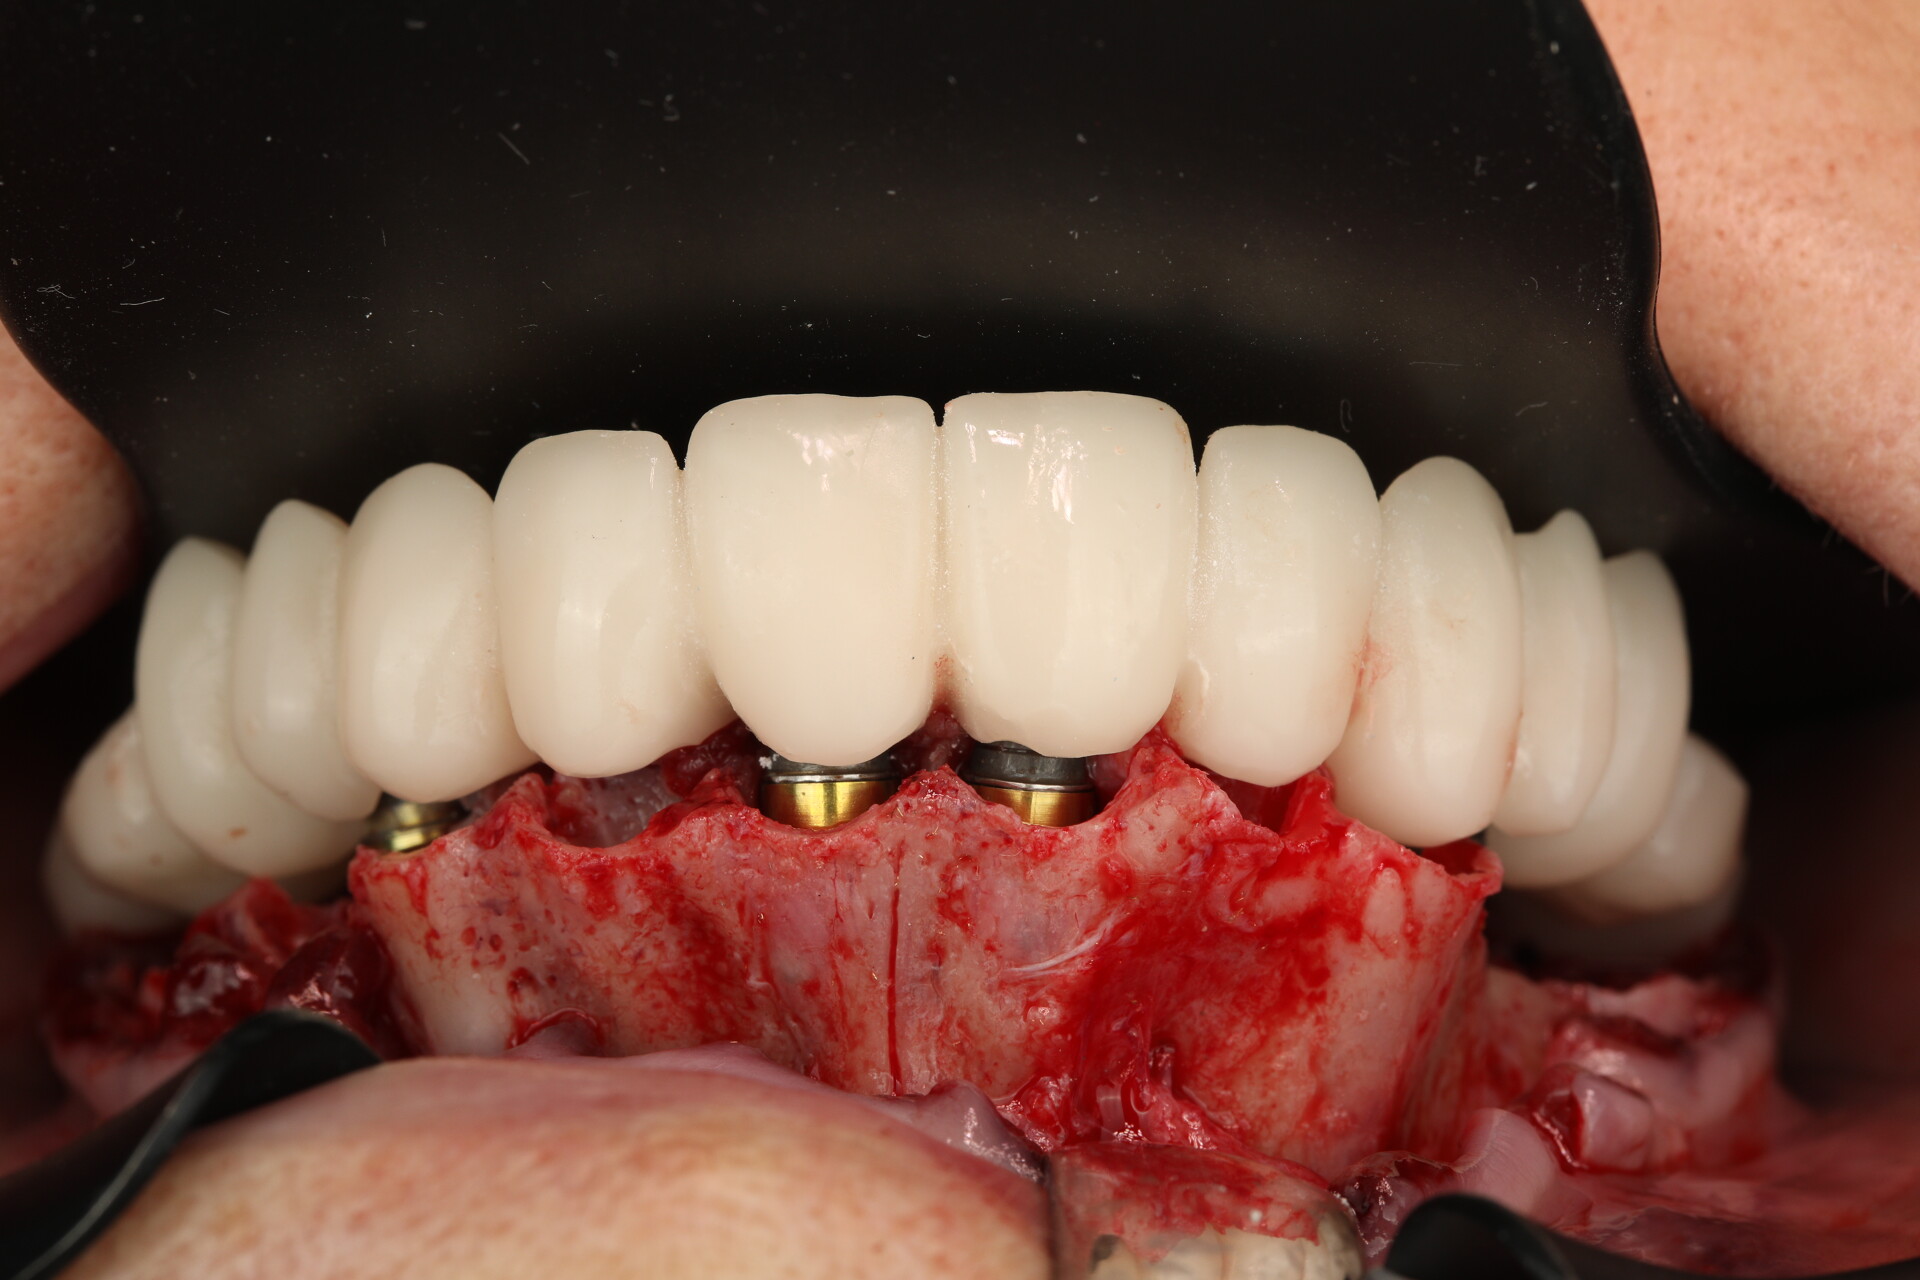

Татьяна Демьяновна Ковалёва

Имплантация. Принципиальное значение костной и мягкой тканей

До

После